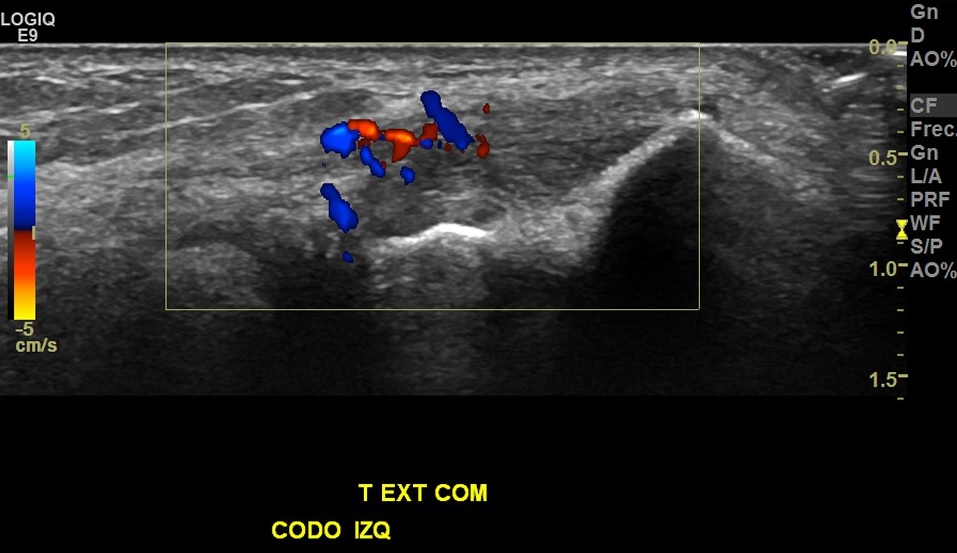

Hallazgos: marcada heterogeneidad de tendón extensor común izquierdo, con foco de desgarro de espesor y ancho parcial en su espesor, con hiperemia al doppler color.